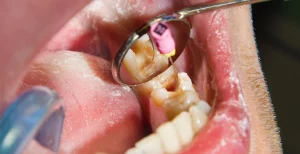

Can You Drink Alcohol After a Tooth Extraction? (9 Safety Tips)

No. You should not drink alcohol after a tooth extraction. The American Dental Association (ADA) recommends avoiding alcohol...